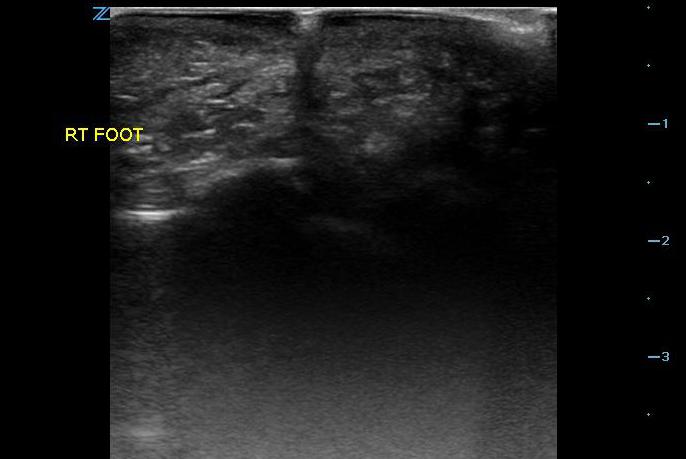

- Figure 2. Glass in foot with shadowing

- Material such as wood, glass, and plastic tends to produce shadowing (Videos 2-4 and Figure 2) which will be visualized in the tissue deep to the foreign body.